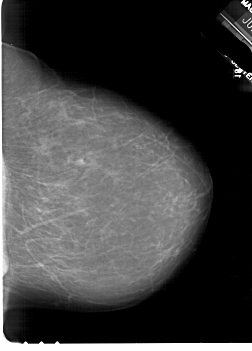

A_1846_1.LEFT_CC

LEFT_CC LINES 6286 PIXELS_PER_LINE 4576 BITS_PER_PIXEL 12 RESOLUTION 43.5 OVERLAY

FILE: A_1846_1.LEFT_CC.OVERLAY

TOTAL_ABNORMALITIES 1

ABNORMALITY 1

LESION_TYPE MASS SHAPE LOBULATED MARGINS ILL_DEFINED

ASSESSMENT 4

SUBTLETY 2

PATHOLOGY BENIGN

TOTAL_OUTLINES 1

BOUNDARY